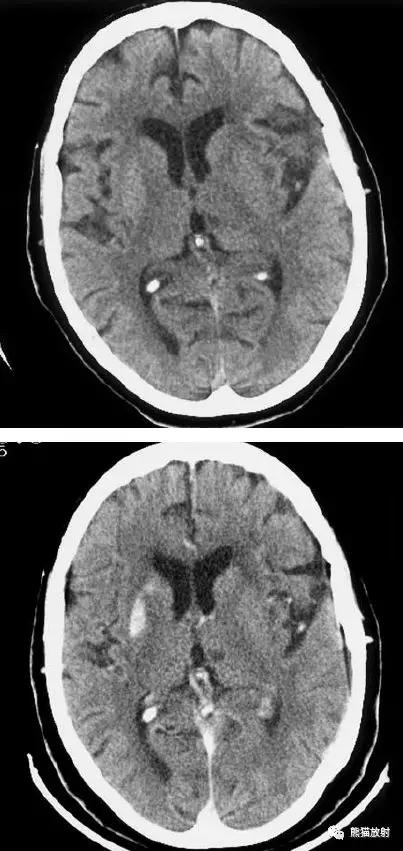

大脑中动脉区梗死:部分梗死,仅累及左侧浅表区域。

左侧大脑中动脉区完全梗死,对邻近的侧脑室产生占位效应;右侧可见其他较小的缺血性低密度区。